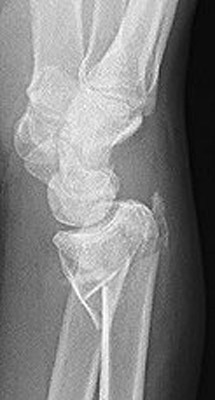

Return to Smith Fracture